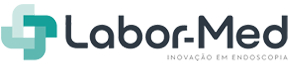

EG-840TP

Gastroscópio Terapêutico Slim Tecnologia de Iluminação Múltipla

Tecnologia 4K O gastroscópio terapêutico slim EG-840TP é equipado com o sensor CMOS e oferece angulação de 160° para baixo, permitindo o acesso a áreas de difícil alcance. Seu canal de trabalho de 3,2 mm proporciona um bom equilíbrio entre desempenho de sucção e controle dos instrumentos inseridos, tornando-o altamente indicado para intervenções terapêuticas avançadas, como a ESD.

Eluxeo | Gastroscospia | Série 800 | Slim | Terapêutico